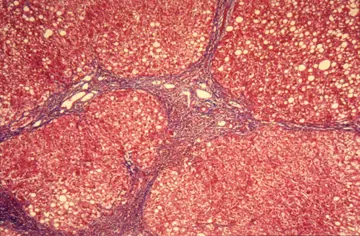

طب داخلی - صفحه 28